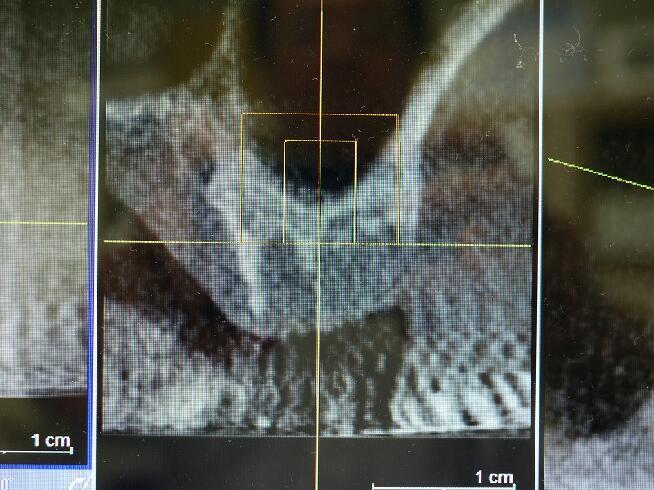

下記の症例では上顎のインプラントを実施するためCT(立体レントゲン)撮影致しました。

その部位の拡大エックス線像です 上顎には他の場所と違い上顎洞という頭を軽くするための空洞があり骨が2~4ミリ程度しかなく、インプラントは大変困難です。